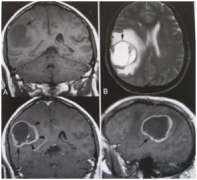

胶质母细胞瘤是星形细胞肿瘤中恶性程度最高的脑胶质瘤,属4级(Ⅳ级)的脑胶质瘤。 胶质母细胞瘤多数原发于脑实质内,亦可呈继发性,由间变性星形细胞瘤进一步恶变转型而成,也可 [阅读全文]

目前虽然有很多关于胶质瘤的分级系统,但是最为常用的还是世界卫生组织(WHO)制定的分级系统。 根据这一分级系统,脑胶质瘤分为1-4级,其中1、2级为低级别胶质瘤,3、4级的恶性程度 [阅读全文]